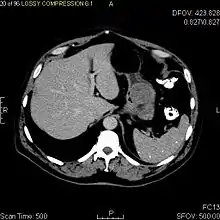

The purpose of radiologic imaging is to locate the lesion, evaluate for signs of invasion and detect metastasis. Features of GIST vary depending on tumor size and organ of origin. The diameter can range from a few millimeters to more than 30 cm. Larger tumors usually cause symptoms in contrast to those found incidentally which tend to be smaller and have better prognosis.[4][12] Large tumors tend to exhibit malignant behavior but small GISTs may also demonstrate clinically aggressive behavior.[13]

As the tumor grows it may project outside the bowel (exophytic growth) and/or inside the bowel (intraluminal growth), but they most commonly grow exophytically such that the bulk of the tumor projects into the abdominal cavity. If the tumor outstrips its blood supply, it can necrose internally, creating a central fluid-filled cavity with bleeding and cavitations that can eventually ulcerate and communicate into the lumen of the bowel. In that case, barium swallow may show an air, air-fluid levels or oral contrast media accumulation within these areas.[13][16] Mucosal ulcerations may also be present. In contrast enhanced CT images, large GISTs appear as heterogeneous masses due to areas of living tumor cells surrounding bleeding, necrosis or cysts, which is radiographically seen as a peripheral enhancement pattern with a low attenuation center.[12] In MRI studies, the degree of necrosis and bleeding affects the signal intensity pattern. Areas of bleeding within the tumor will vary its signal intensity depending on how long ago the bleeding occurred. The solid portions of the tumor are typically low signal intensity on T1-weighted images, are high signal intensity on T2-weighted images and enhance after administration of gadolinium. Signal-intensity voids are present if there is gas within areas of necrotic tumor.[14][17][18]

Malignancy is characterized by local invasion and metastases, usually to the liver, omentum and peritoneum. However, cases of metastases to bone, pleura, lungs and retroperitoneum have been seen. In distinction to gastric adenocarcinoma or gastric/small bowel lymphoma, malignant lymphadenopathy (swollen lymph nodes) is uncommon (<10%) and thus imaging usually shows absence of lymph node enlargement.[12] If metastases are not present, other radiologic features suggesting malignancy include: size (>5 cm), heterogeneous enhancement after contrast administration and ulcerations.[4][12][19] Also, overtly malignant behavior (in distinction to malignant potential of lesser degree) is less commonly seen in gastric tumors, with a ratio of behaviorally benign to overtly malignant of 3-5:1.[4] Even if radiographic malignant features are present, these findings may also represent other tumors and definitive diagnosis must be made immunochemically.